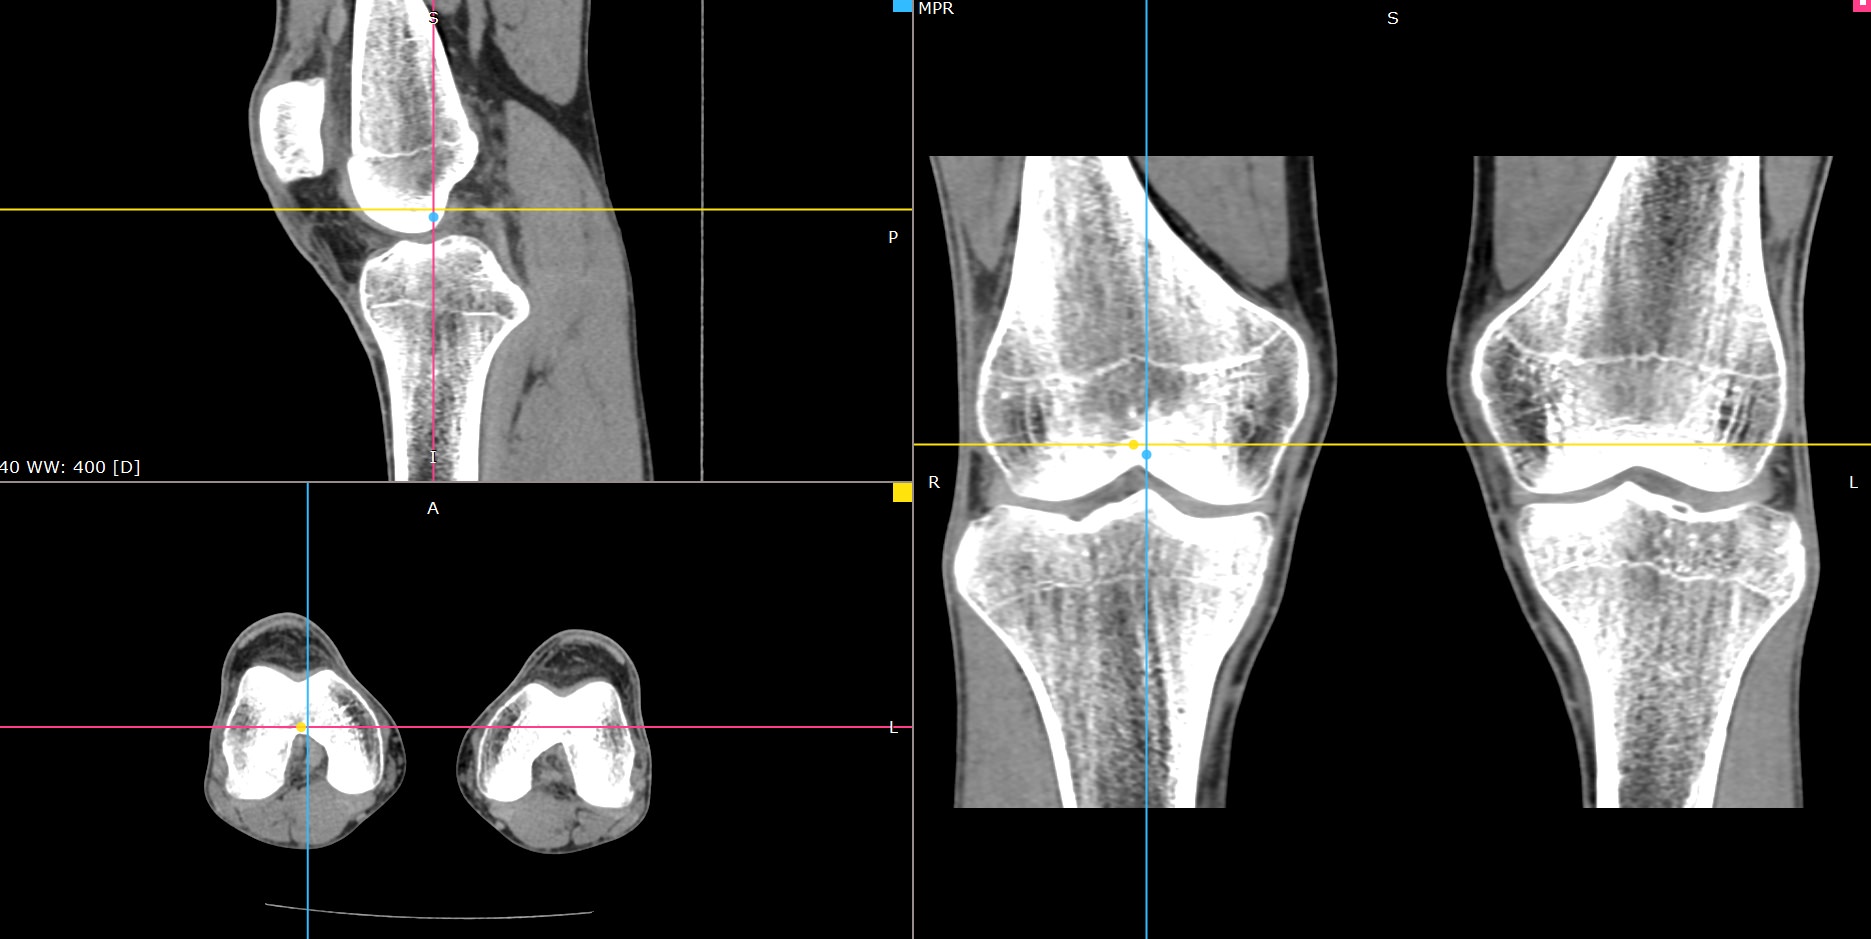

Мультиспиральная компьютерная томография является современным лучевым методом исследования, который позволяет с помощью рентгеновского излучения получить посрезовые снимки и после цифровой обработки создать объемные модели исследуемой области в мельчайших подробностях. Рентгеновские лучи в большей степени поглощаются плотными тканями организма, поэтому на снимках хорошо визуализируются кости скелета. Для более детальной оценки состояния мягкотканных структур зачастую проводится контрастное усиление.

В наших медицинских центрах КТ мягких тканей конечностей выполняется на современных мультиспиральных компьютерных томографах экспертного уровня TOSHIBA AQUILION. Аппараты послойно сканируют область исследования, одномоментно выполняя множество тончайших срезов. В результате получаются снимки высокого качества и трехмерные модели с изображением костного скелета и мягких тканей конечностей. При этом методика скоростного мультисрезового сканирования обеспечивает минимальную дозу рентгеновского облучения для пациента.